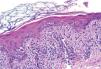

Se realizó una biopsia de una de las lesiones de la axila izquierda que mostró una epidermis con discreta hiperqueratosis y papilomatosis. Destacaba en la capa basal, e incluso en niveles medios, el aumento de tamaño de los queratinocitos con núcleos grandes, atípicos, a veces binucleados, nucleolos evidentes y mitosis. En la dermis papilar y media existía un infiltrado inflamatorio de distribución perivascular, compuesto por linfocitos y escasos neutrófilos, que contactaba en zonas con la capa basal, lo que provocaba discretas hendiduras, e incluso penetraba en pequeños grupos en la epidermis (figs. 2 y 3).

Se estableció el diagnóstico de erupción intertriginosa con dermatitis de interfase y dismaduración epidérmica causada por DLP y se decidió continuar con el fármaco reduciendo la dosis a 40 mg/m2, sin apreciar recurrencia del cuadro tras la tercera infusión.